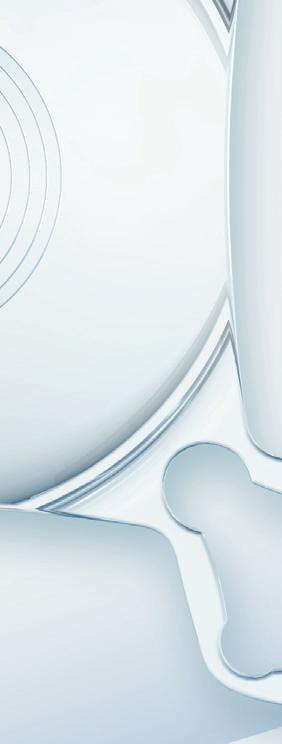

A novel procedure promises to make allogenic intrastromal ring implantation easier and more effective.

The introduction of corneal allogenic intrastromal ring segment or CAIRS by Dr Soosan Jacob in the mid-late 2010s was a welcome addition in treating non-CXL-eligible patients with keratoconus, an important step forward from the classic PMMA intrastromal rings (with far fewer side effects in severity and frequency), and a new alternative to corneal transplantation.

Despite the innovative approach and the ironclad rationale, introducing soft corneal tissue in the stroma is not an easy task, leading experts to strive for a way to make the procedure less challenging. Dr Shady Awwad was the first to propose stiffening the corneal rings through a process of dehydration, an idea that made the insertion procedure a bit easier but lacked efficacy by comparison.

Inserting a CAIRS has a steep learning curve, since the surgeon is dealing with soft tissue. Even using the technique conceived by Dr Awwad has some procedural difficulties, Dr Cosimo Mazzotta observed. Dehydrating a CAIRS can be helpful in terms of insertion, added Dr Marco Zagari, but surgeons end up with a stiff ring that might not have the same efficacy as the non-processed one.

According to both Mazzotta and Zagari, finding common ground between ease and efficacy was the key to improving this procedure, and the best way to achieve this goal was to use riboflavin and UV light.

To find the lowest common denominator, Dr Zagari noted it was necessary to improve Dr Jacob’s idea through Dr Awwad’s mindset. Keeping that in mind, Dr Mazzotta added the decision was to make allogenic intrastromal rings stronger, but not stiffer, using corneal cross-linking.

Processed with a vector-based customised nomogram, the rings obtain a ‘gummy bear’-like solidity, effectively exceeding the dehydrated rings in terms of ease of use. Dr Mazzotta observed this is unheard of in the field of corneal surgery, a completely distinct perspective that generated something brand new and feasible for surgeons globally.

It is a solution that offers high rates of repeatability and opens previously impossible new prospects, Dr Zagari said. Everything is calculated using topographic data from both donor and recipient and precisely cut with a femtosecond laser—based on a specific nomogram designed by the authors and vectorial analysis provided by MS-39 CSO tomography.

Soon it will be possible to calibrate levels of elasticity and elastic recoil with the potential to have a ring that is perfectly tailored to the patient’s needs, he added.

The PMMA-like consistency of cross-linked CAIRS makes the insertion like the non-allogenic intrastromal rings, underlining how the procedure does not require a second point of access. Moreover, the low or absent immunogenicity of cross-linked and decellularised collagen completely reduces the risk of rejection.

Drs Mazotta and Zagari conducted a preclinical study with the Siena Crosslinking Centre and the Veneto Eye Bank Foundation, with its medical director Diego Ponzin. The study has been presented to the Siena Crosslinking Centre ethical committee, before entering the clinical phase, Dr Mazzotta said. For more information, see C Mazzotta, et al., “Crosslinked All-Femtosecond laser-cut Corneal Allogenic Intracorneal Ring Segments (AFXL CAIRS): Pilot Ex-Vivo and In-Vivo Study in Italy,” Preprints, (2024): 2024081945. As of today, the first all femtolaser-cut X-linked (AFXL) CAIRS has already been implanted in patients with keratoconus in Italy, with very promising results and well-responding patients, Dr Zagari concluded. Dr Mazzotta will present a course covering this topic, “What’s New in Early Diagnosis, Pathophysiology, and Prevention Strategies of Keratoconus,” which takes place Monday, 14:00–15:30, 8.1 P.